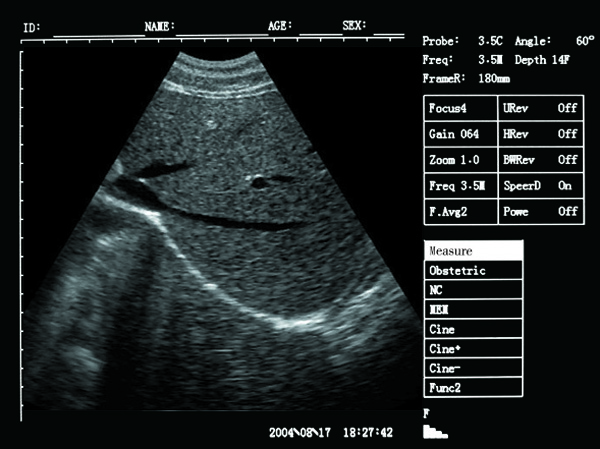

Scan results :